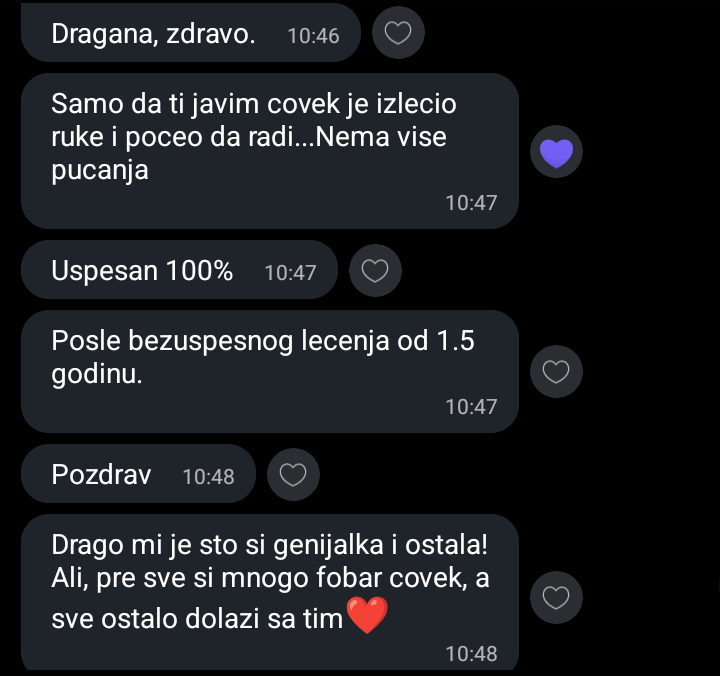

Prof. dr Dragana Pavlović svojim znanjem i iskustvom iz oblasti fitoterapije, aromaterapije i farmacije stojiiza svih HCinnovative proizvoda. Dragana je rođena Nišlika, a svoje osnovne i poslediplomske studije završila je na Farmaceutskom fakultetu u Beogradu. Na istom fakultetu je odbranila i specijalistički rad iz Kontrole i primene lekovitih biljaka. Njeno usavršavanje iz savremene primene lekovitih biljaka obuhvata i edukaciju iz Kliničke aromaterapije Minesota Univerziteta. Dugogodišnji je član (u periodu 2018-2025. i predsednik) Udruženja farmaceuta nišavsko-pirotskog regiona (FNP). Akreditovani je predavač (od strane Zdravstvenog saveta Srbije) za veliki broj edukacija lekara, farmaceuta, stomatologa i zdravstvenih tehničara. Na Univerzitetu u Nišu je redovni profesor i odgovorni nastavnik na predmetima Biljni lekovi, Samonega i samolečenje, Lekoviti prirodni proizvodi.